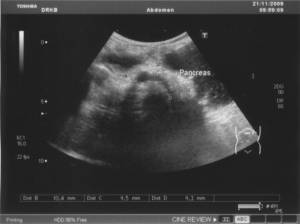

Рис. 4.4. Хронический панкреатит у ребенка 8 лет.

Эхогенность паренхимы поджелудочной железы повышена в значительной степени

Ультразвуковое исследование проводится утром, натощак.

Поджелудочная железа, размеры натощак: головка 9,8 мм,

тело 6,9 мм, хвост 7,2 мм, гиперэхогенная, контуры нечеткие, гиперэхогенные

включения 1,4 мм (кисты?). Диаметр селезеночной вены 5,5 мм, скорость линейного

кровотока 0,19 м/сек, объёмная скорость кровотока 0,24 л/мин.

Поджелудочная железа постпрандиально: головка 10,4 мм,

тело 9,5 мм., хвост 9,2 мм. Диаметр селезеночной вены 3,8 мм, скорость

линейного кровотока 0,17 м/сек , объёмная скорость кровотока 0,22 л/мин.

Заключение:

отмечается уменьшение размеров поджелудочной железы натощак (норма по

Дворяковскому в 7–9 лет: головка 16 мм, тело13 мм, хвост 13 мм). Неоднородная,

наличие кист. Диаметр СВ уменьшен. ЛСК и ОСК снижена.